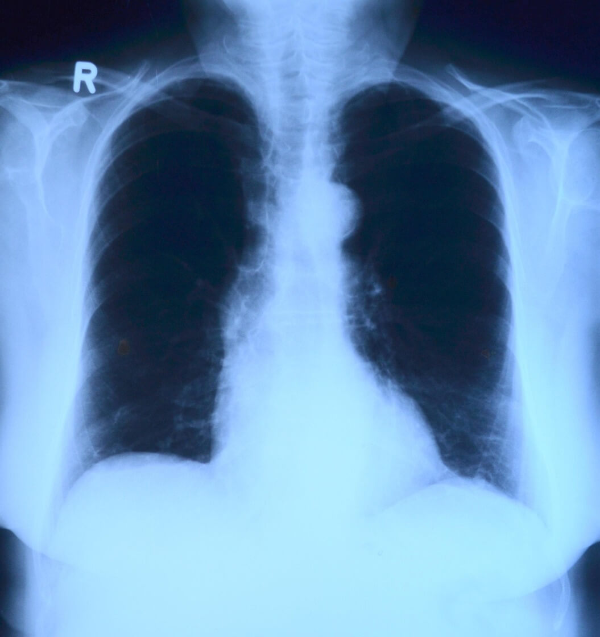

5. 오른쪽 등 통증 의심되는 병 ④ 폐, 호흡기 질환

오른쪽 등 통증이 숨 쉴 때 심해진다면 호흡기 문제도 배제할 수 없습니다. 특히 갑작스럽게 시작된 통증이라면 더욱 주의가 필요합니다.

- 폐렴

- 늑막염

- 기흉

기침이나 호흡 곤란, 숨을 깊게 들이마실 때 통증이 심해진다면 빠른 진료가 중요합니다. 이 경우에는 단순 통증으로 참기보다는 즉시 병원을 찾는 것이 안전합니다.